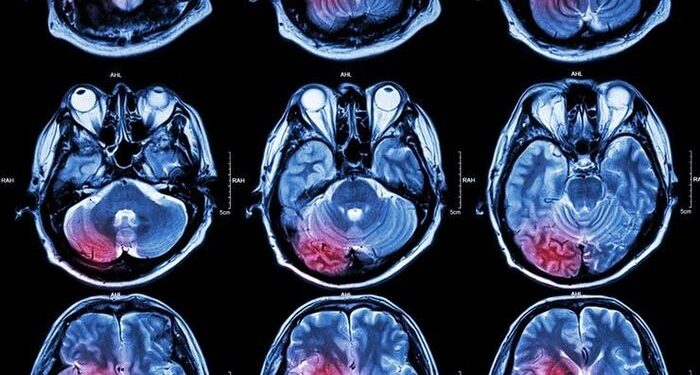

Theo tiến sĩ Peter Bentley, việc AI có thể ghi lại giấc mơ không còn là câu hỏi “nếu”, mà là câu hỏi “khi nào”. Trên thực tế, các nhà khoa học đã và đang tìm cách ghi lại sóng não và giấc mơ thông qua các công nghệ như máy quét cộng hưởng từ chức năng (fMRI).

Dữ liệu fMRI có thể là yếu tố giúp hiện thực hóa việc ghi lại giấc mơ bằng AI.

Một nghiên cứu của Nhật Bản năm ngoái đã chứng minh fMRI có thể phân loại các hoạt động khác nhau trong tâm trí đang ngủ. Dựa trên cơ sở này, các chuyên gia tin rằng một ngày nào đó, chúng ta có thể sử dụng công nghệ này để tạo ra AI có khả năng ghi lại và tái hiện giấc mơ.